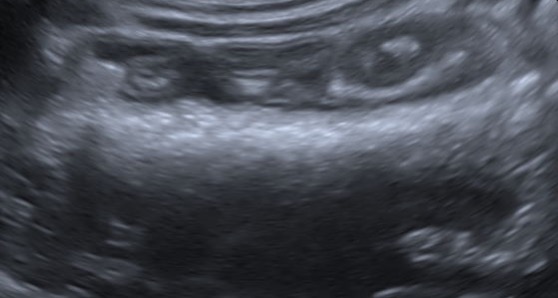

超音波検査 アコーディオン状に引き攣れた消化管と中に太めの紐状異物を確認